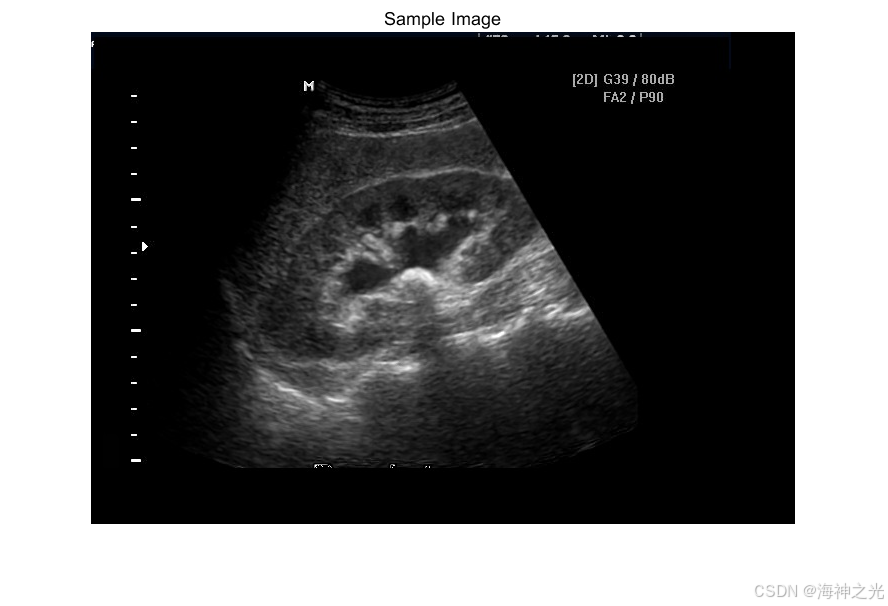

⛄三、运行结果